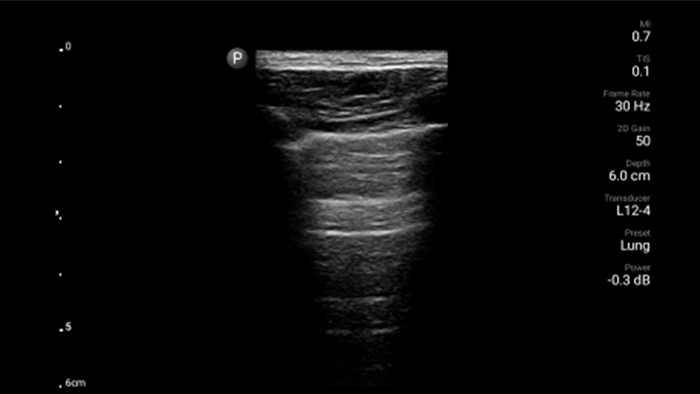

System Lumify do badań POCUS może służyć do wykrywania rurki dotchawiczej w tchawicy, pomagać podczas pilnych zabiegów konikotomii, diagnostyce wysięku opłucnowego oraz chorób pęcherzyków płucnych.

System Lumify do badań POCUS może być niezwykle cennym narzędziem do oceny stanu treści żołądka, które może obniżyć ryzyko jej aspiracji do płuc, a tym samym ryzyko powikłań po zastosowaniu znieczulenia.